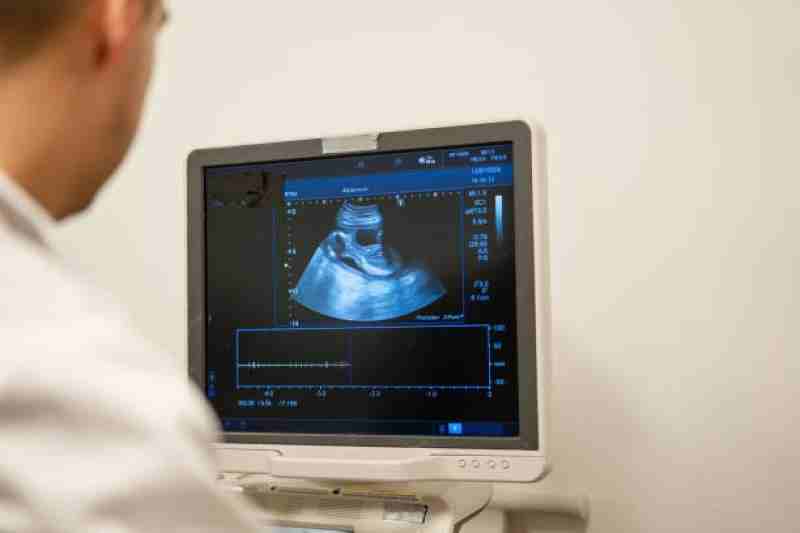

The liver is your body's detox center-- it filters toxins, stores nutrients, and helps digest fats. Liver cancer happens when abnormal cells grow uncontrollably in the liver tissue.

2. When is Liver Surgery Recommended?

3. How Doctors Decide the Right Type of Surgery

Choosing the right surgical option isn't one-size-fits-all. The best liver transplant specialist in Delhi carefully evaluates:

Tumor size and location

Liver function (through tests like the Child-Pugh score).

Overall health condition.

Whether there's cirrhosis (liver scarring).

This careful evaluation ensures that surgery offers the best chance for cure or long-term survival.